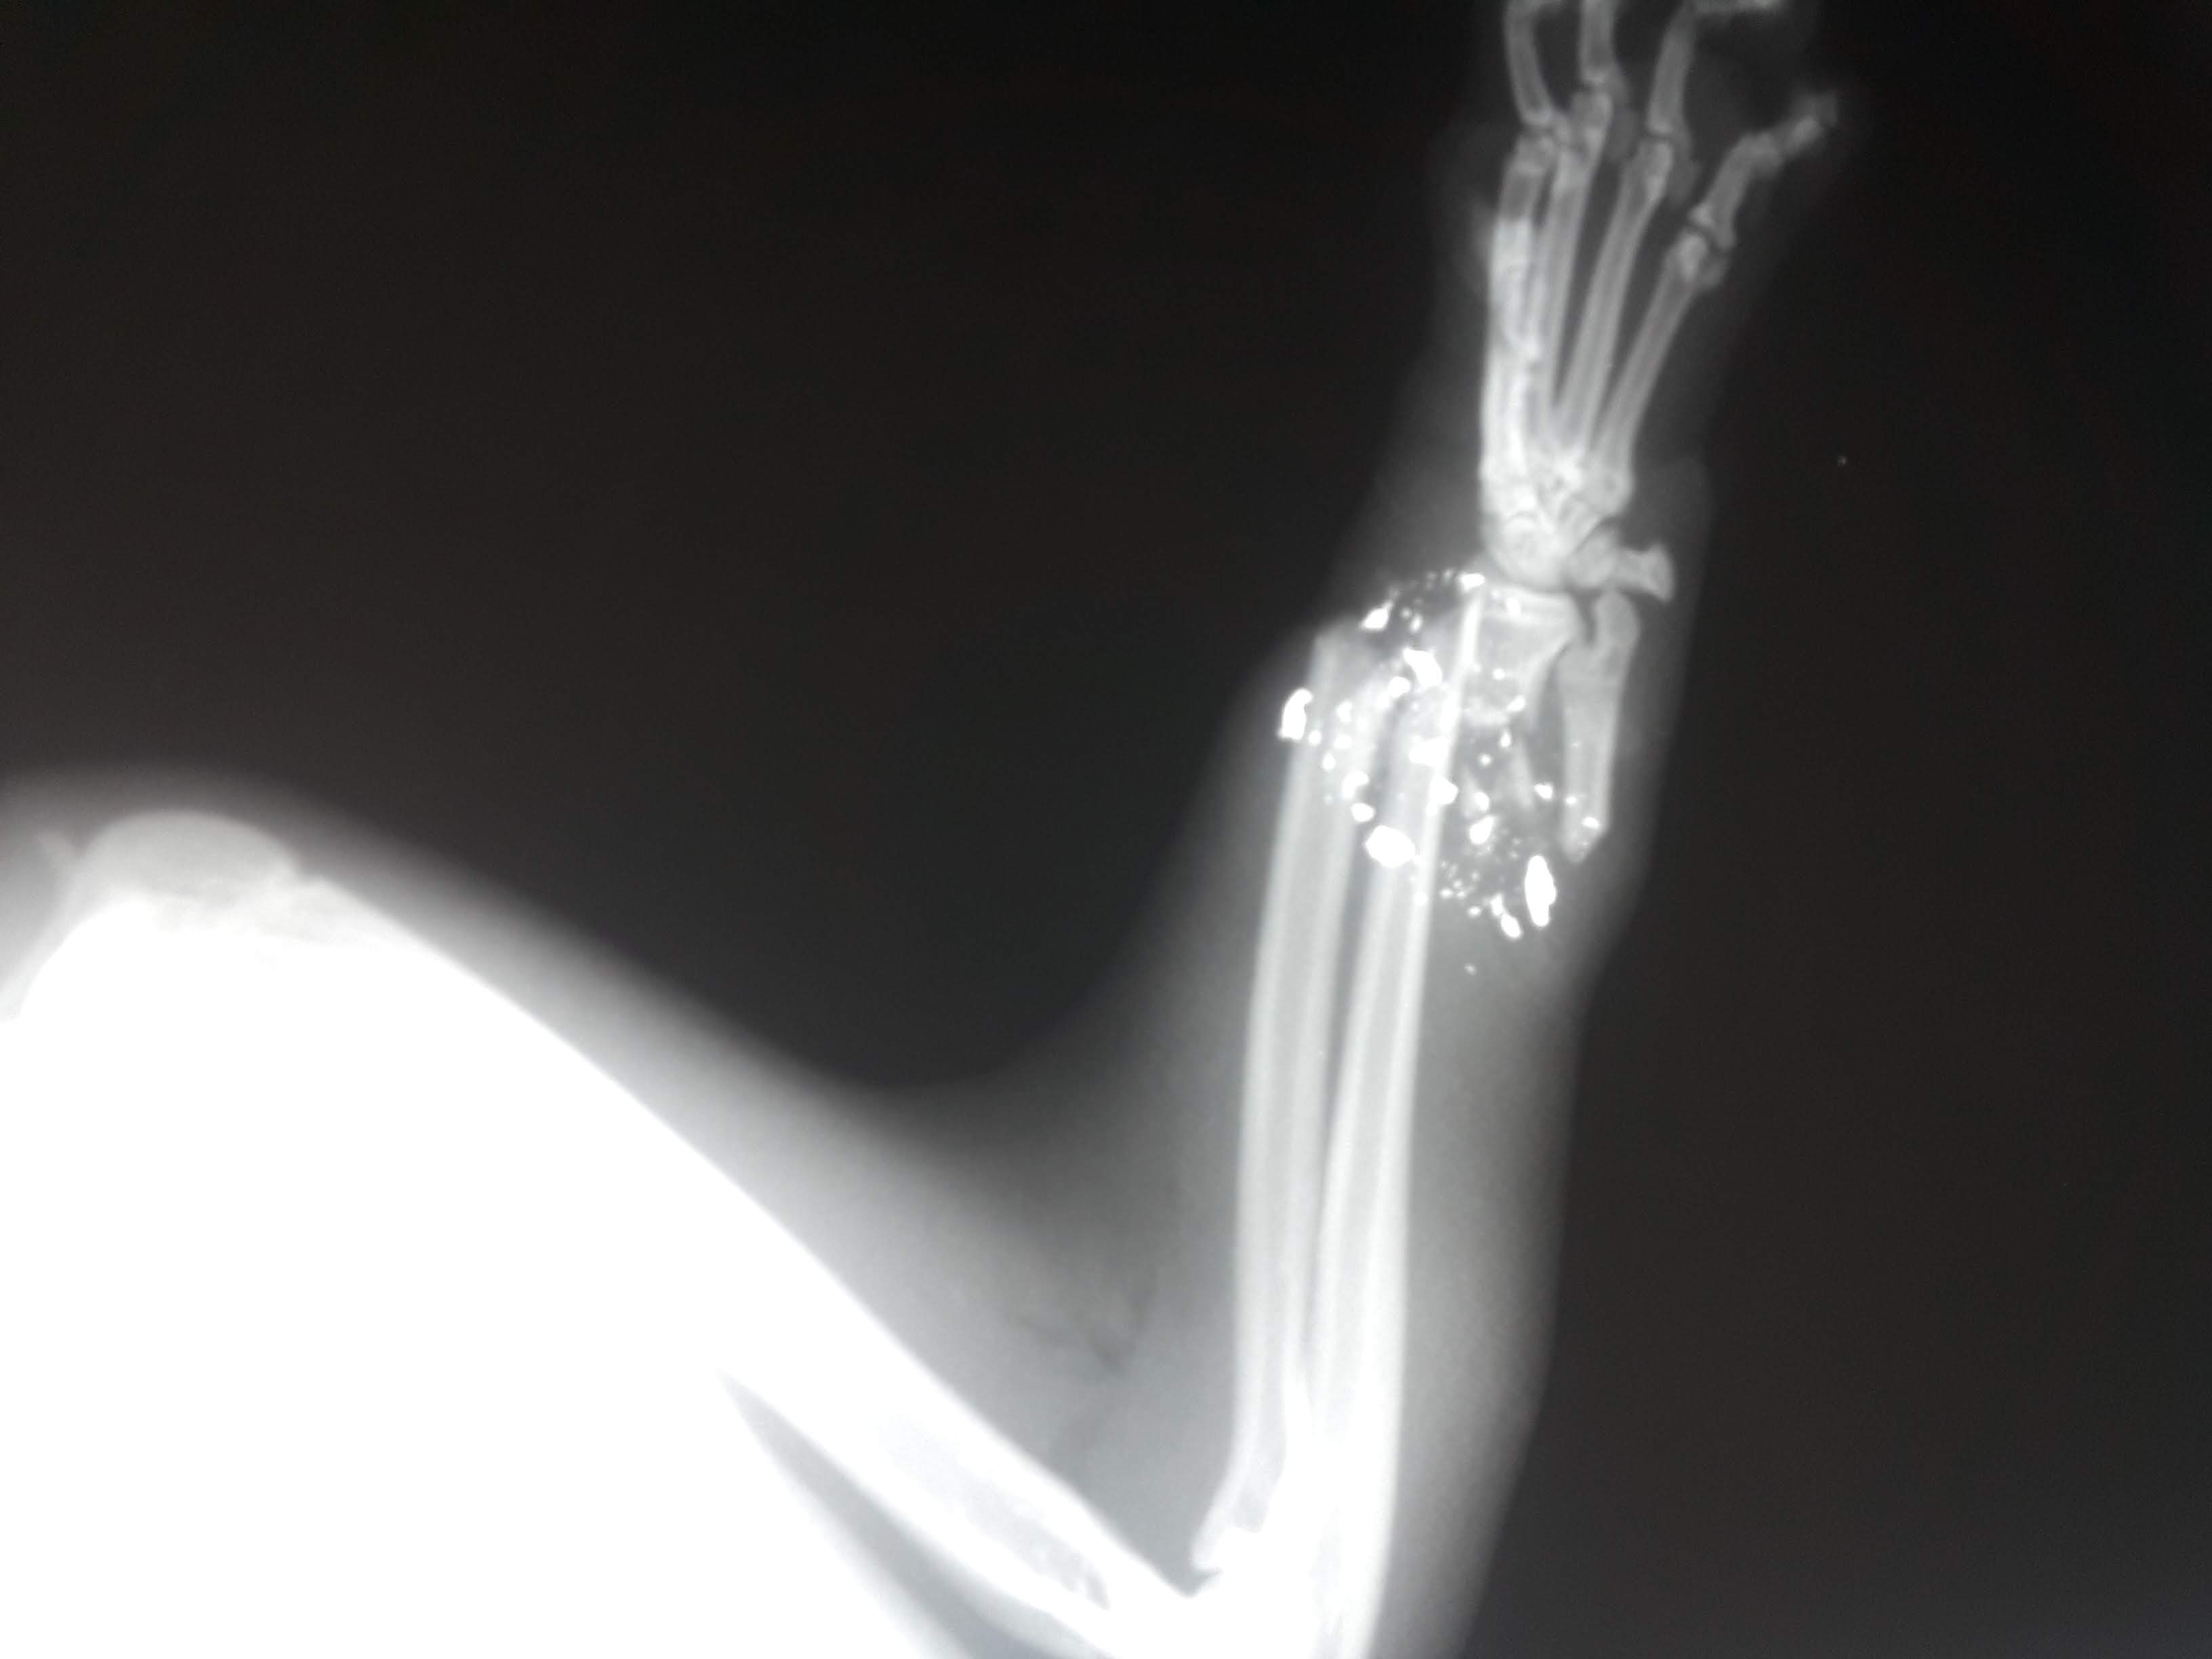

Jose Feneque, DVM (46)

Veterinarian